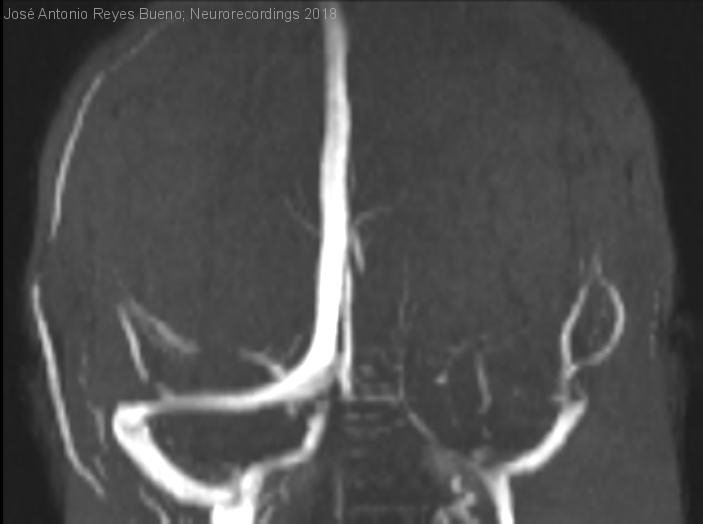

Gran trombosis venosa cerebral

Mujer | 53 años

Diagnóstico final: trombosis venosa cerebral

Mujer con antecedentes de migraña episódica infrecuente sin auras, obesidad y tabaquismo, que acude por tercera vez a urgencias por cuadro de dolor de cabeza muy intenso  de dos semanas de evolución, de rápida progresión...